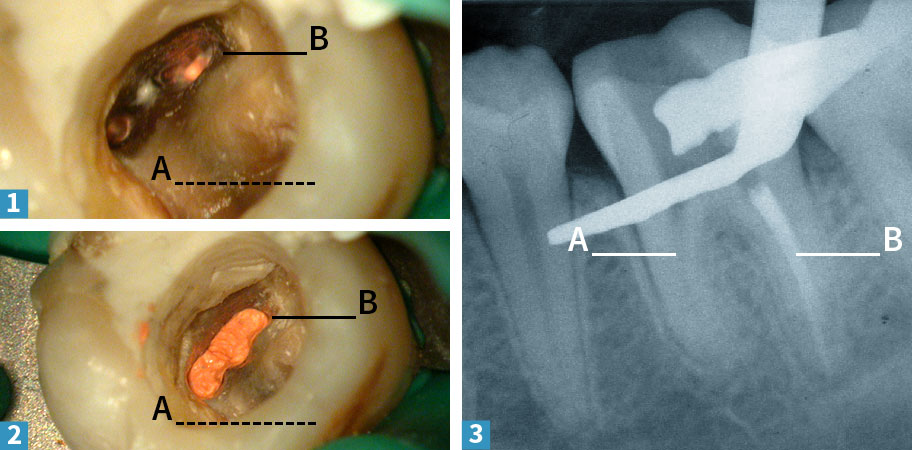

Jeder Zahnwurzel verfügt über einen Hohlraum, der das Zahnmark und den Zahnnerv enthält. Entzündet sich das Zahnmark oder stirbt es gar ab, muss es entfernt werden. Ziel der Wurzelbehandlung ist es – einfach formuliert – das Gewebe zu entfernen, den Hohlraum sauberzumachen und anschließend dicht zu verschließen. Unser Beispiel-Zahn ist ein unterer Backenzahn und hat zwei Wurzeln, hier A und B gekennzeichnet.

1 Im ersten Arbeitsschritt haben wir die provisorische Füllung abgetragen und das Zahnmark entfernt. Durch das Operationsmikroskop erkennt man nun in der einen Wurzel (A) zwei deutlich voneinander getrennte Kanaleingänge.

2 Die andere Wurzel (B) unseres Zahnes enthält einen breiten Wurzelkanal.

3 In der starken Vergrößerung sieht man, dass sich der breite Kanal in der Tiefe aufzweigt. Insgesamt müssen also vier Kanäle in den beiden Wurzeln behandelt werden. Die Kanäle werden gereinigt und mit einer antimikrobiellen Spülung sauber gemacht.